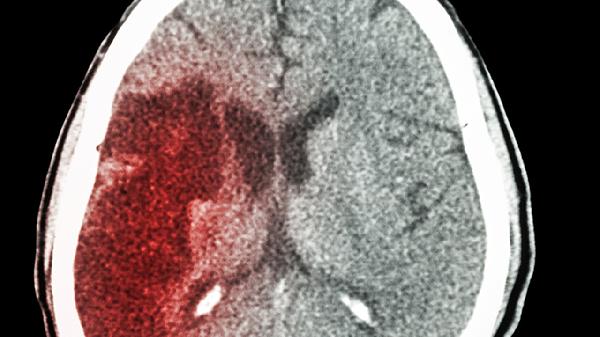

脑出血的应急处理方法主要有保持患者安静、避免移动头部、立即拨打急救电话、清理口腔异物、监测生命体征等。脑出血通常由高血压、脑血管畸形、外伤等因素引起,需尽快就医干预。

脑出血急性期应绝对卧床休息,转运时使用硬质担架避免颠簸。恢复期需控制血压在安全范围,避免用力排便、剧烈咳嗽等增加颅内压的行为。饮食以低盐、低脂、易消化的流质或半流质为主,循序渐进进行肢体康复训练。定期复查头部CT监测血肿吸收情况,严格遵医嘱服用降压药如苯磺酸氨氯地平片、缬沙坦胶囊等预防再出血。